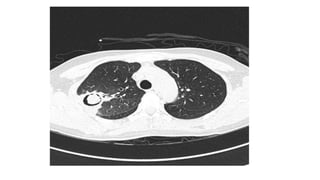

Successive axial views within the lung window showing Aspergillus nodules, of variable size and borders, and a

fungus ball filling a cavity with a wall of variable thickness in a patient with pre-existing bronchiectasis and

cicatricial atelectasis of the mi...

David W. Denning et al. Eur Respir J 2016;47:45-68

©2016 by European Respiratory Society

Copyrights apply

• #27 Successive axial views within the lung window showing Aspergillus nodules, of variable size and borders, and a fungus ball filling a cavity with a wall of variable thickness in a patient with pre-existing bronchiectasis and cicatricial atelectasis of the middle lobe.